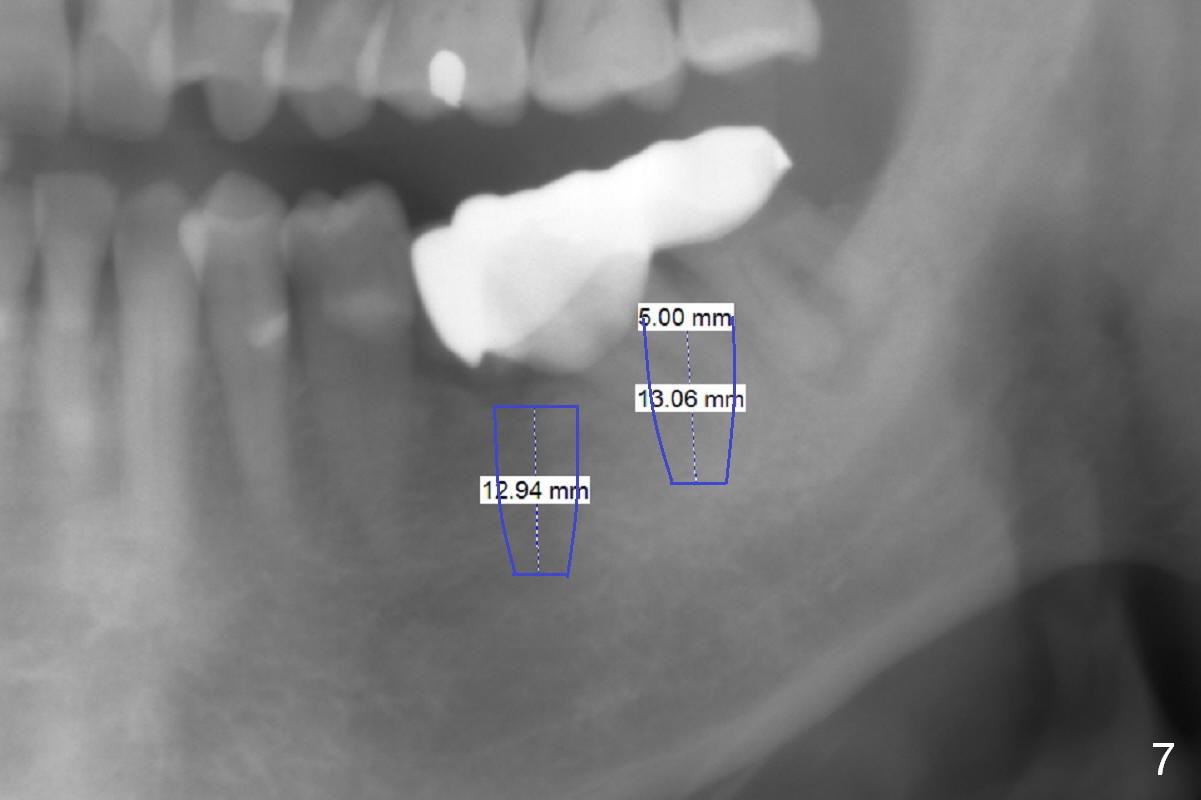

A 82-year-old man has pain in the lower left bridge. There is a buccal apical fistula associated with the tooth #17 (Fig.1). An immediate implant will be placed at #17 after bridge removal (Fig.2,3 blue). Once it osteointegrates, it will be used an anchorage (direct (instead of indirect), most efficient) to upright the tooth #18 (change the longitudinal axis from red line to purple one (Fig.4); white circle: center of resistance (rotation)). Then an implant will be placed at #19 (white rectangle).

Take Alginate impression and keep it moist. It will be used as a stent for temporization later on. After the tooth #17 is extracted with Clindamycin treatment, a FC dummy implant (5x9 mm) will be placed, followed by 6x4(2) mm abutment (Fig.3,4 pink). If there is severe vertical height issue, change to Magicore. Due to schedule conflict, prepare UF for this case instead.